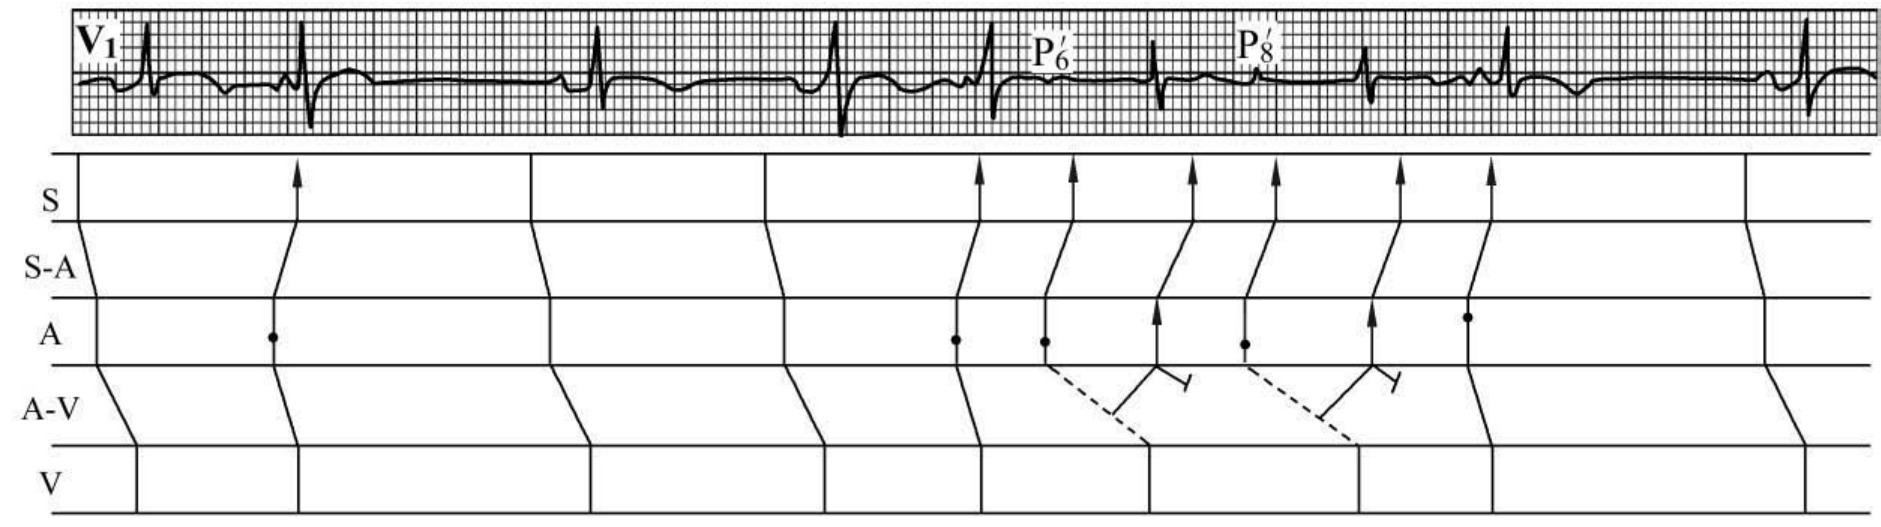

(二)重复出现窦性或房性反复搏动,即呈P(P')-QRS-P或P(P')-QRS-P-QRS或P

(P')-P序列的心房回波(图60-89)。

img1251

图60-89 窦性心动过缓、双源性房性期前收缩,其中一源房性期前收缩引发房性反复搏动(P6'、P8')